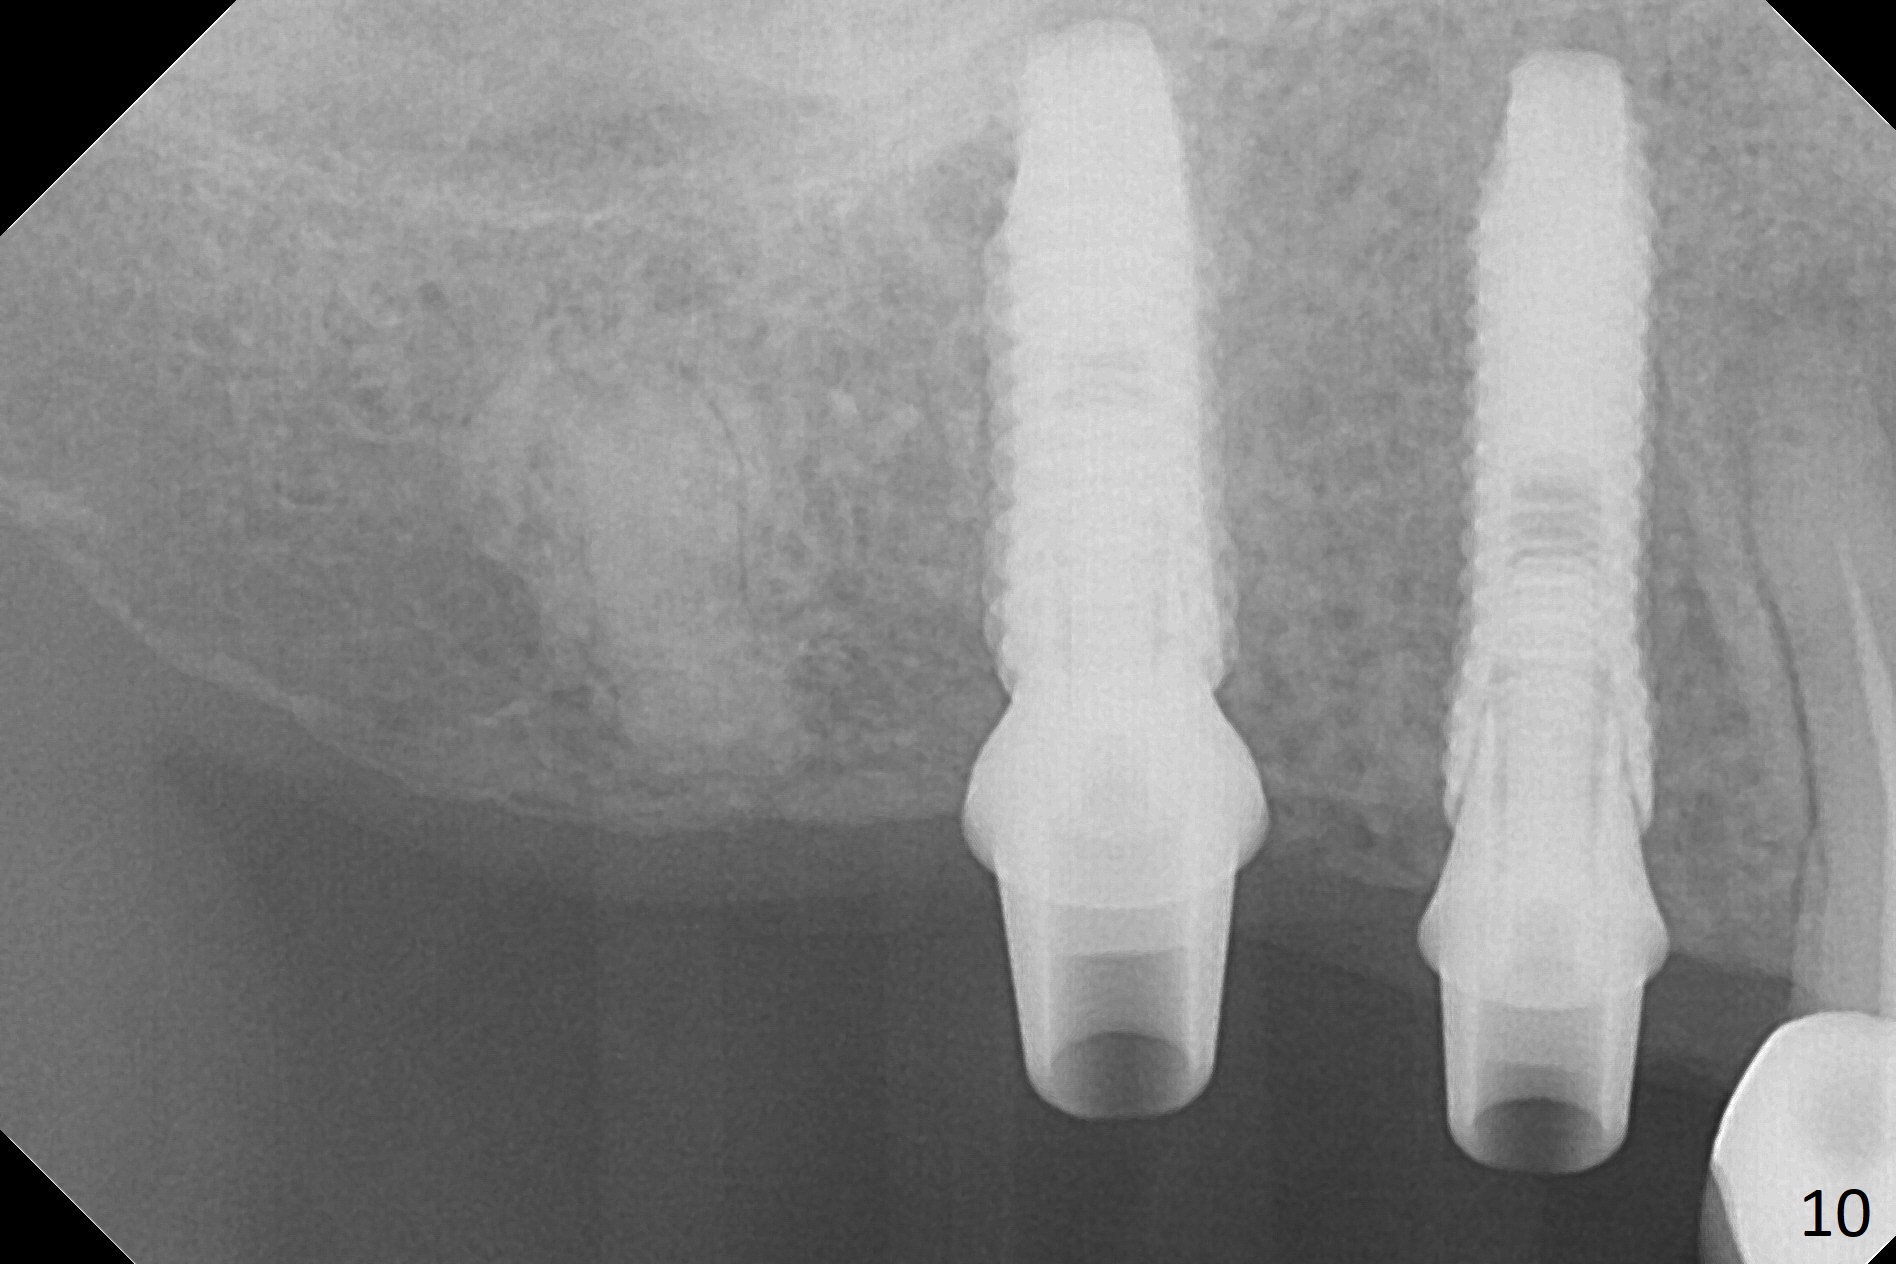

The ridge at #3,4 is wide (Fig.1). A surgical stent is placed (Fig.2) for initial osteotomy (Fig.3). When the stent is removed, the osteotomies need to move palatal (Fig.4 arrows). As two of 1.2 mm drills are in place (Fig.5), mesiodistal trajectories are found off (Fig.6). After the trajectories are corrected (Fig.7), the depth cannot be determined with PA (Fig.8, as compared to Pan (Fig.9)). Following 4.3 and 3.2 mm final drills at #3 and 4, 4.5x13 and 3.8x15 mm implants are placed with insertion torque of 35 and 50 Ncm, followed by 5.5x4(3) and 4.5x4(2) mm abutments (Fig.10). BWs show incomplete placement of the implant at #4 distal (Fig.11,12). Later the implant is placed ~ .5 mm deeper. Periodontal dressing is applied postop. CT-assisted surgical guide must be more efficient for this case with wide ridge. There is no bone loss around the implants 3 moths postop

(Fig.13).